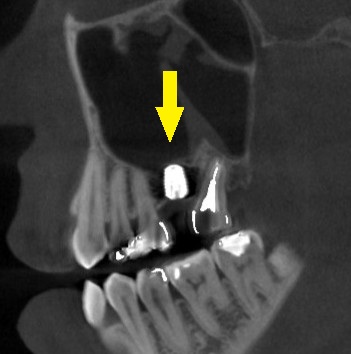

ご納得いただけましたので、本日、ワイドショートインプラント、直径5.0mm、長さ7mmのインプラントを埋入しました。

下の写真、2段目が手術前のCT、3段目が手術後のCTです。